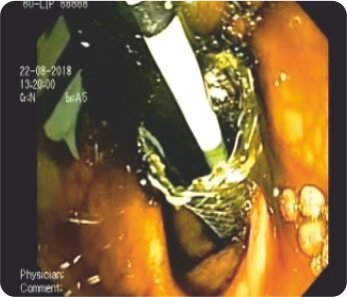

CBD এর EUS নির্দেশিত পাংচার ডুডেনামের প্রথম অংশ থেকে করা হয়েছিল। কোল্যাঞ্জিওগ্রামের পরে, ট্র্যাক্টটি সিস্টোটোম দিয়ে ক্রমান্বয়ে 10 ফারেনহাইট পর্যন্ত প্রসারিত করা হয়েছিল এবং একটি 60x10 মিমি সম্পূর্ণ আচ্ছাদিত বিলিয়ারি স্টেন্ট স্থাপন করা হয়েছিল যা D1 এবং CBD এর সাথে সংযোগ স্থাপন করে। একটি 7F 7cm ডবল পিগটেল প্লাস্টিক বিলিয়ারি স্টেন্ট মেটাল স্টেন্টের মধ্যে স্থাপন করা হয়েছিল যাতে এর স্থানচ্যুতি রোধ করা হয়। কোন পেরিপ্রোসিডারাল জটিলতা ছিল না। এক সপ্তাহের মধ্যে তার বিলিরুবিন স্বাভাবিক হয়ে যায় এবং তাকে কেমোথেরাপি করা হয়।

D1-এ FCSEMS-এর সাথে প্লাস্টিক স্টেন্ট